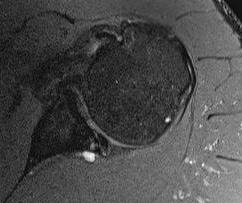

MRI

Spinoglenoid cyst

Spinoglenoid cyst with SLAP tear and posterosuperior labral tear